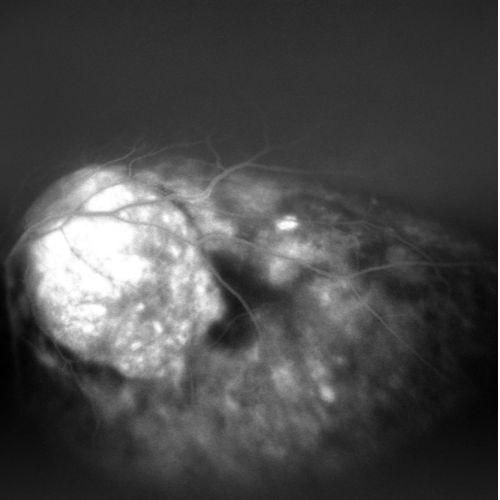

Retromode

Verde

Rosso